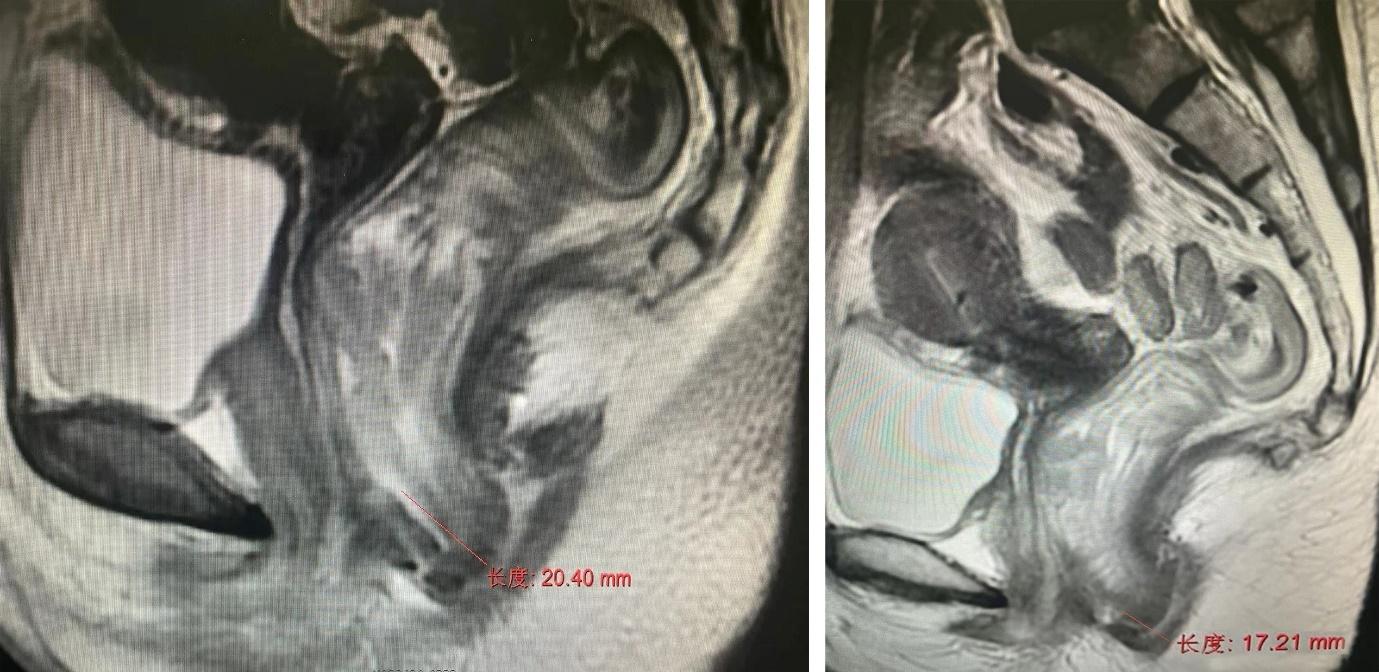

▲影像显示许女士超低位直肠癌距肛门<2cm,肿瘤下缘跟肛缘仅17.21mm